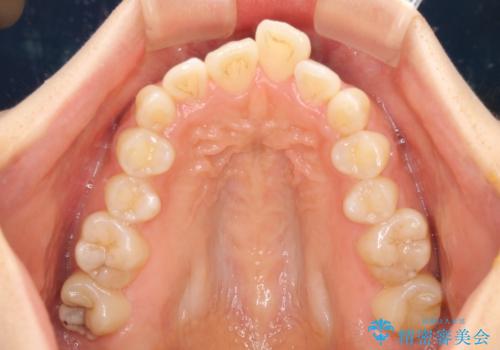

- 飛び出した前歯と口元の突出感を気にして来院された患者様です。

奥歯の咬み合わせを見ると、上顎が下顎に対して相対的に前方にありました。

口元の突出感を改善するためには、上顎臼歯を後方に移動させた咬み合わせにする必要があります。

インビザライン単体で改善することも可能ですが、達成する可能性が高くないため、カリエールディスタライザーという補助装置を併用して、より確実性を上げることとしました。

奥歯の咬み合わせを改善しながら、並行してインビザラインで歯列を整えることとしました。